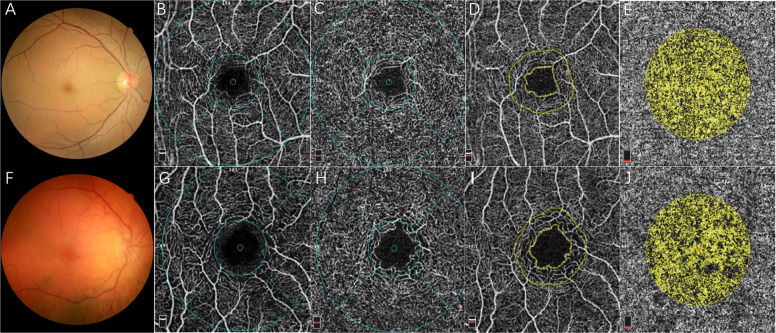

Vessel density (VD) of each region was calculated as the vessel area divided by the region area and nine regions of interest are shown in Fig. 1. The area, perimeter, and acircularity index of FAZ were also calculated automatically. The choroid flow area was analyzed in a 1-mm radius circle centered on the fovea at the level of choriocapillaris.

Fig. 1. Representative instances of convalescent VKH disease.

a Fundus photograph of the right eye from a 31-year-old man, without sunset glow fundus. f Fundus photography of the right eye from a 48-year-old man, indicating obvious sunset glow fundus. b, g Superficial vascular plexus of two representative patients. The whole image was divided into the superior and inferior region. Moreover, the foveal region was defined as a 1 mm radius circle centered on the fovea. The area between 1 mm radius and 3 mm radius circle centered on the fovea was defined as parafoveal region and the parafovea was divided into four equal sectors named temporal, superior, nasal, and inferior quadrant. c, h Deep vascular plexus of two representative patients. d, i The foveal avascular zone of two representative patients. e, j The flow area of choroid was calculated in a 1-mm radius circle centered on the fovea at the level of choriocapillaris.